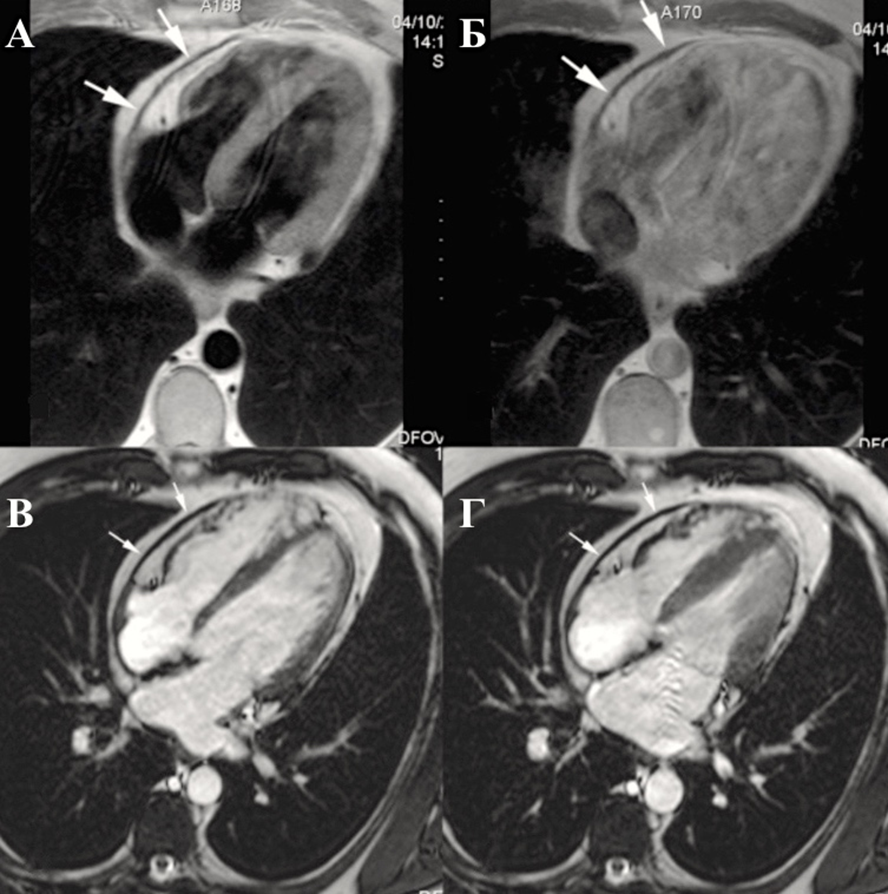

3. Магнитно-резонансная томография

Как и при КТ, МРТ позволяет выполнять прямой анализ количества жидкости в перикарде на основании трехмерной реконструкции ее объема.

МРТ выполняется в режимах «темной» крови и кино-МРТ. Для выявления воспаления листков перикарда и для выявления опухолей перикарда применяется методика МРТ с контрастированием — парамагнитные контрастные средства (гадолинием) в раннюю фазу и в отсроченную (late gadolinium enhancement — LGE).

Показания к назначению МРТ сердца:

Рекомендовано выполнение МРТ или КТ пациентам с перикардитом при необходимости уточнения данных эхокардиографии (артефакты, плохое ультразвуковое «окно»), оценки характера выпота в перикард (диагностика выпота с высокобелковым, геморрагическим содержимым), выявления воспаления листков перикарда и оценки его выраженности, выявления и количественной оценки дисфункции камер сердца, вызванных тампонадой или констрикцией, исключения опухолевого поражения перикарда, миокардита, при противопоказаниях к КТ [155, 156, 157, 158].

Констриктивный перикардит характеризуется утолщением перикарда, которое больше выражено со стороны правого желудочка и передней атривентрикулярной борозды (Приложение А3, рис. А3-11) [156].

Утолщенный перикард имеет слабую интенсивность сигнала не только на Т1- и Т2-взвешенной спин-эхо МРТ, но и на киноизображениях; в терминальной стадии констриктивного перикардита введения парамагнитных контрастных средств (гадолиний- содержащих) не приводит к увеличению детализации изображения (Приложение А3, рис. А3-12) [158].

Косвенными признаками констриктивного перикардита будут: расширение предсердий, дилатация полых и печеночных вен, асцит и плеврит.

В случаях констриктивного перикардита выявляются значительное утолщение перикарда, между листками которого обнаруживаются спайки c очагами казеозного перерождения и превращения в рубцовую ткань. Также возможно обнаружение обызвествления околосердечной сумки.